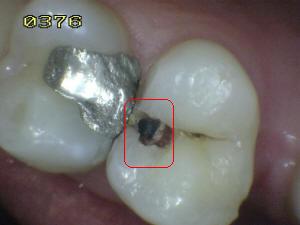

¿Determine los códigos pertinentes a cada imagen?

Click en el hipervínculo: Para comparar el resultado de su diagnóstico